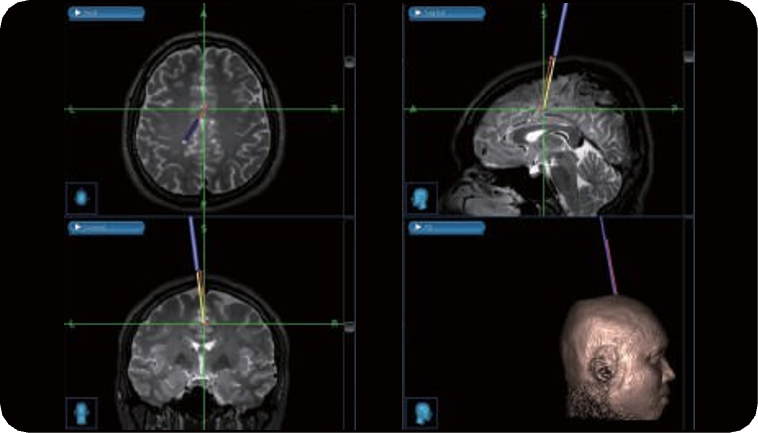

NaviIFUS® incorporates a custom-designed multi-channel hemispherical phased-array ultrasound to generate focused treatment units capable of covering a large tumor volume. The location of the treatment units is determined using pre-treatment planning software that analyzes the patient’s CT/MRI images. Guidance of FUS energy to the desired treatment area is done using a neuronavigation tracking system, allowing for more precise treatment.

Personalize Treatment Planning

•Based on patient’s MR and CT scans

•Physicians determine ROIs and transducer positionings

•Transcranial penetration calculation

FUS Focal Point Guidance

•Integrate with Neuronavigation System